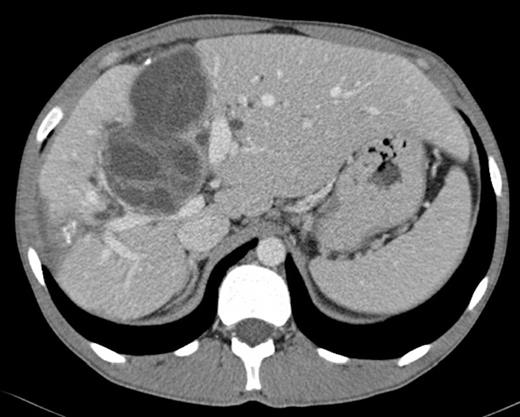

Abdominal CT scan: multiple hydatid cysts in the right lobe of the liver, one of them near the hepatic confluence

Laboratory investigations showed a slight anaemia, elevation of serum bilirrubin (conjugated 10.6 mg/dl), alkaline phosphatase (959 U/L), gamma-glutamyl transpeptidase (755 U/L). Hydatid serology was positive. Abdominal ultrasound demonstrated multiple cystic lesions spread in the liver, splenic hilum and peritoneal cavity. CT-scan confirmed the presence of numerous hydatid cysts, in different stages of development (type I-IV of Gharbi Classification), ranging from 3 to 8 cm in diameter, with 3 involving the right lobe of the liver and segment 4 (Fig.1). The splenic hilum contained a 4 cm cyst, and 9 more cysts were described in peritoneal cavity: near the gallbladder, in the root of the mesentery, in the right iliac fossa and in the Douglas pouch (Fig. 2). Cholangio pancreatography (MRCP) showed intra-hepatic bile ducts dilatation. Cholangiography (ERCP) was attempted without success. Pre-operative albendazole therapy (10 mg/Kg) was prescribed for 4 weeks.